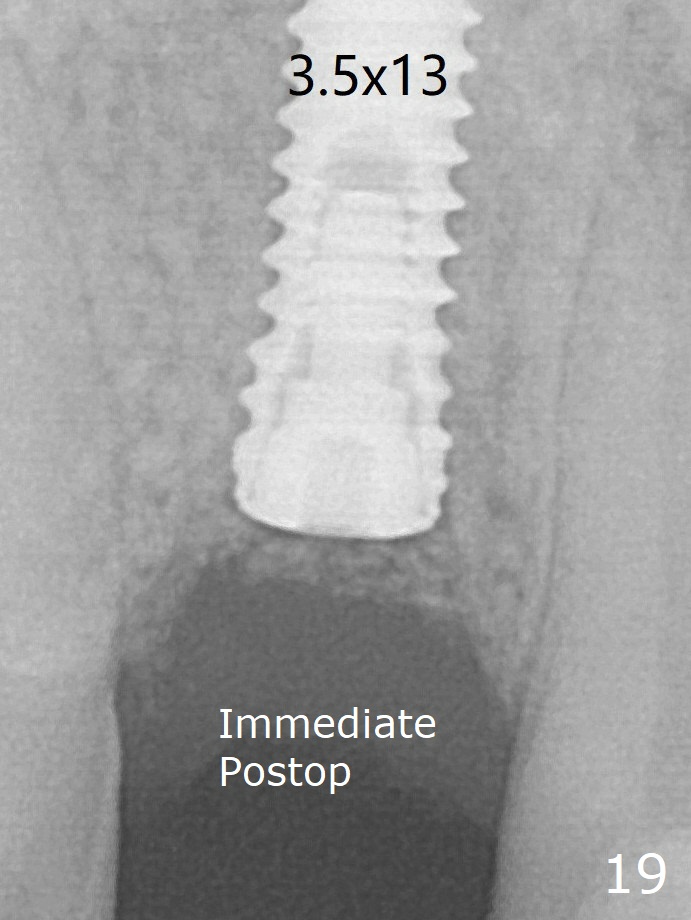

Finally using Lindamann bur, the osteotomy is changed so that a 3.5x13 mm 2-piece implant does not need an angled abutment to establish occlusion (Fig.19). There is one palatal thread exposure. Allograft is placed circumferentially, followed by Human Amnion-Chorion Allograft and Collagen Plug. A 4.5x5.5(3) mm appears to be seated incompletely with a gap between the abutment and the implant (Fig.24 <, overtightened?). A provisional is fabricated after heavy palatal reduction. Two months later, the provisional fractures. After repositioning the abutment with complete seating and torque (Fig.25), impression is taken.